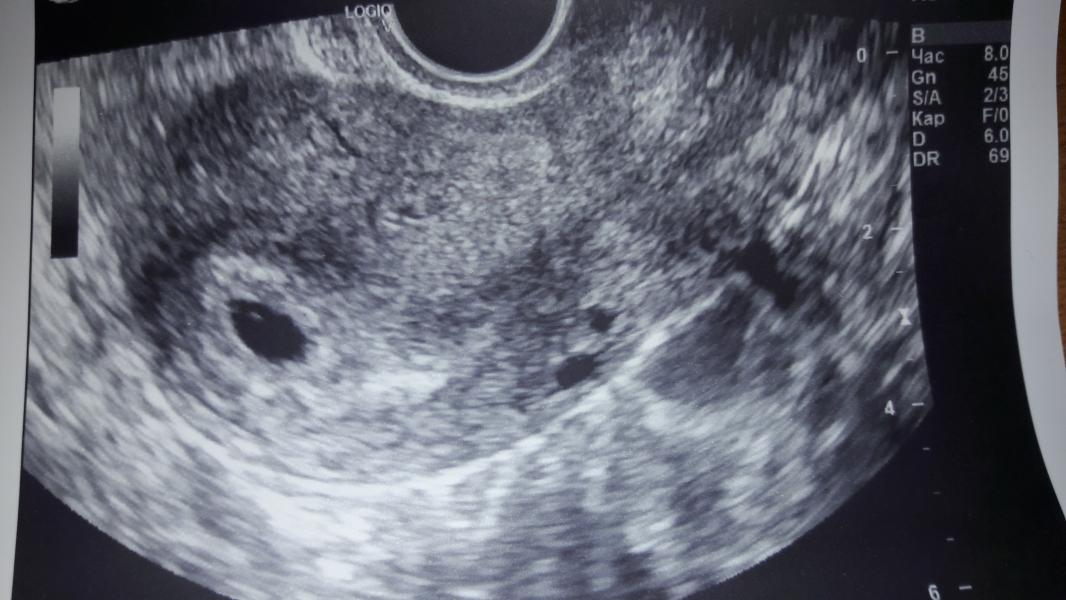

вот фото узи. 5,1 неделя по узи. 6,1 по месячным.

в диагнозе написано, что эмбриона нет. и желточный мешок тоже не визуализируется.

но на фото есть какая то точка-полосочка(если вы видите) что это может быть?